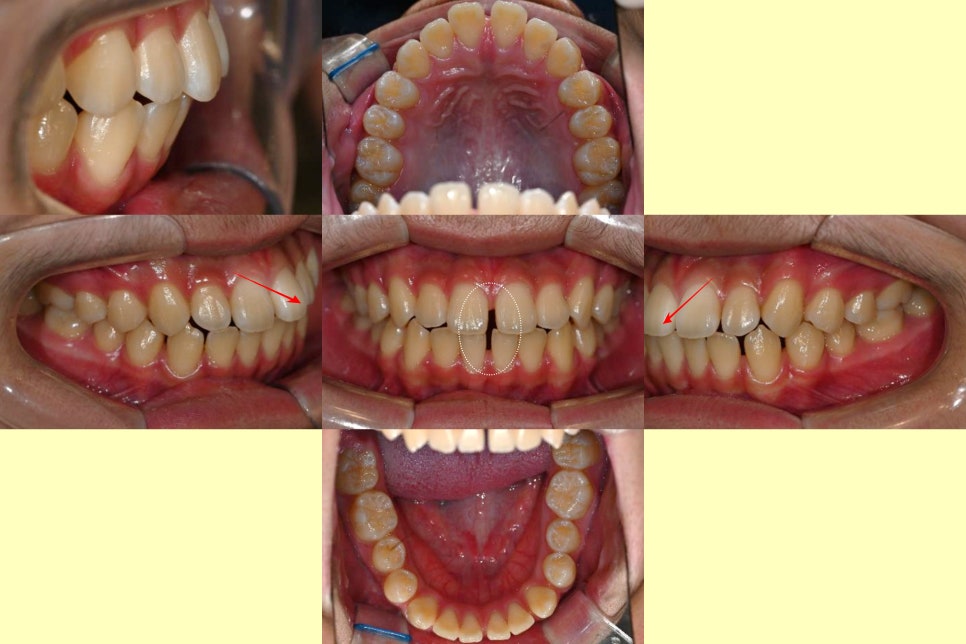

2024.01.08

앞니 사이 벌어짐 과 함께

입술 쪽으로 뻐드러진 각도마저 관찰된다면

혀내밀기 습관을 가진 환자의 전형적인

앞니 형태라 볼 수 있습니다.

혀의 강한 힘에 의해 튀어나온 아랫니가

절단교합과 반대교합까지 유발할 수 있습니다.

안모를 봤을 때, 턱끝이 왼쪽으로 치우친

비대칭 양상이 관찰되었으나,(왼쪽)

눈확아래선을 기준으로 보면

골격의 비대칭은 심하지 않은 편입니다.(오른쪽)

어금니 교합이 정상인 점(1급 관계),

위턱과 아래턱이

조화로운 상태인 점(Skeletal class I)

등을 고려하여

비발치 교정을 결정했습니다.

단, 혀내밀기 습관으로 발생한

공간을 폐쇄하고 앞니를 배열할 때

돌출입이 해소되는 정도에 따라

작은 어금니 발치 여부를 판단하기로 했습니다.